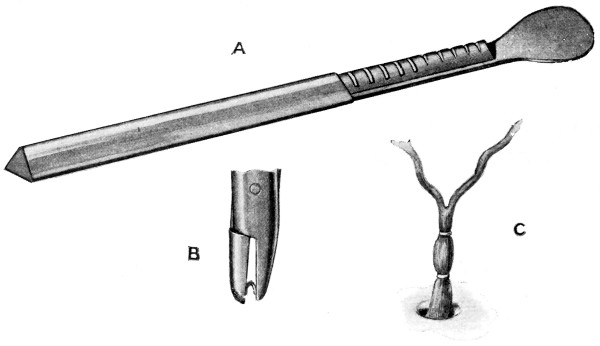

Fig. 6. Cushing’s Clips. A, The holder of the clips; B, A clip ready to be applied; C, Two clips applied to the middle meningeal artery.

Hæmorrhage from the middle meningeal artery may be controlled by ligature or torsion, and added to these methods we have one other, recently introduced by Cushing—silver wire ‘clips’. These clips[19] are U-shaped, loaded on a magazine, picked up as required in the jaws of a specially indented forceps, and clipped on to the vessel—usually one on either side of the bleeding-point.

Fig. 11. Horsley’s Disk or Bone Elevator.

Fig. 12. Horsley’s Dural Separator.

Fig. 13. Keen-Hoffmann’s Craniectomy Forceps.

Fig. 14.

Lane’s Fulcrum

Craniectomy Forceps.

Fig. 15.

Horsley’s Gouge

Forceps.

Fig. 16. De Vilbiss’s Craniectomy Forceps.

Previous to any attempt at enlargement of the trephine hole, the dura mater must be separated from the bone with the aid of Horsley’s dural separator or other suitable instrument. Of the many patterns of craniectomy forceps, the following will be found to suit all requirements:—

The visceral blade is introduced between the dura and the bone and ‘morcellement’ carried out. It is essential[25] that the surgeon should not be too greedy, resting content with the removal of small fragments at a time.

They possess great mechanical advantage and are mainly suited for the rapid removal of large portions of bone.

This instrument is mainly utilized in the smoothing and refreshing of sharp edges of bone, and in the ‘morcellement’ of the thinner portions of the skull—temporal and cerebellar regions.

A clever contrivance whereby the operator is enabled to cut a narrow channel in the bone. Mainly utilized in the formation of the osteoplastic flap.